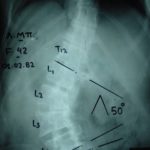

Εικ.1: Προσθι-οπισθίες ακτινογραφίας της θωρακο-οσφυικής μοίρας της σπονδυλικής στήλης.

Παρατηρείται σταθερή και σημαντική επιδείνωση του σκολιωτικού κυρτώματος από την ηλικία των 37 ετών (38°) εώς 64 ετών (85°). Η πάσχουσα λάμβανε μεγάλη ποσότητα αναλγητικών και υποβάλλετο σε συνεχή φυσιοθεραπευτική αγωγή, χωρίς καμία βελτίωση των συμπτωμάτων της.